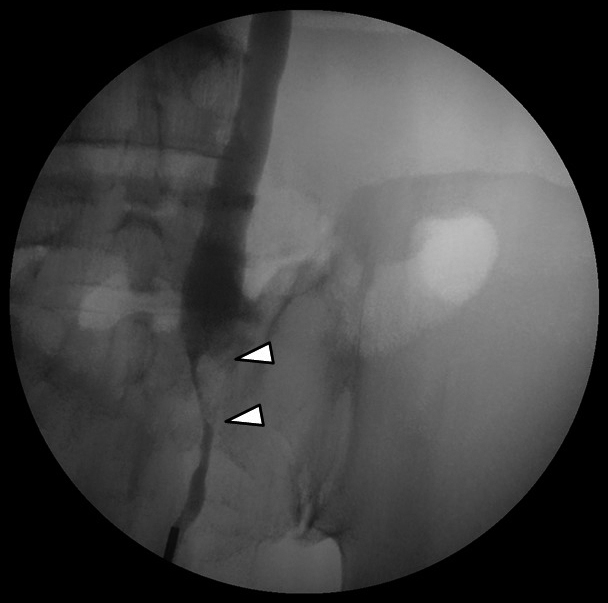

逆行性腎盂尿管造影検査所見:左尿管に狭窄像を認めた(Fig. 4矢頭).術中操作のために尿管ステントを留置した.

Retrograde pyelogram of the left ureter showed stenosis of the left ureter (arrowheads).